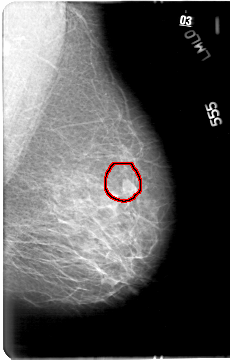

FILE: D_4033_1.LEFT_MLO.OVERLAY

TOTAL_ABNORMALITIES 1

ABNORMALITY 1

LESION_TYPE MASS SHAPE IRREGULAR MARGINS ILL_DEFINED

ASSESSMENT 0

SUBTLETY 5

PATHOLOGY BENIGN

TOTAL_OUTLINES 1

BOUNDARY

D_4033_1.LEFT_MLO

LEFT_MLO LINES 5386 PIXELS_PER_LINE 3436 BITS_PER_PIXEL 12 RESOLUTION 43.5 OVERLAY